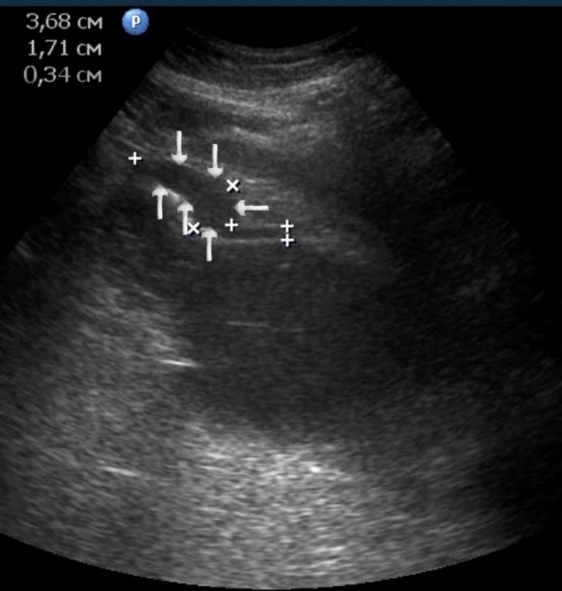

T2 stage of diffuse carcinoma was recorded in 14 cases – among them 5 cases of ulcerating forms, 5 cases of infiltrative ulcerative forms and 4 cases of diffuse infiltrative forms. Gastroscopy diagnosis was established in all 10 cases of ulcerative and infiltrative ulcerative forms of gastric carcinomas and in 3 cases of diffuse infiltrative forms. Ultrasound diagnosis was established in 13 cases of diffuse carcinoma, except for one case where the location of the ulcerative form was in the fundus of the stomach (Figure 8, Figure 9, Figure 10).

Figure 10.The gastric carcinoma of diffuse infiltrative form. An area with a local thickening up to 1,7 cm, a length of 3,68 cm, is visualized on the anterior wall of the antrum (arrows). The thickening of the normal stomach wall is 0,34 cm.